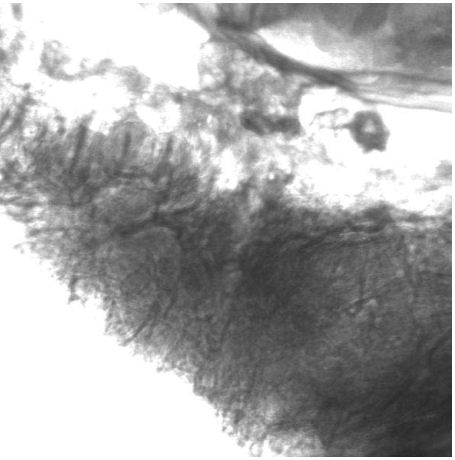

In the second part of this study, laser scanning microscopy was compared with TEWL measurements, analyzing the wound healing process after application of the suction blister technique. The disadvantage of the TEWL measurement was that it could not be applied during the first stage of the wound healing process, because the skin surface of the lesion was covered by wound secretion. The corresponding high water evaporation disturbs the TEWL measurement. Furthermore, the application of a wound healing cream is able to disturb the TEWL measurement. On the contrary, the application of in vivo laser scanning microscopy allows the determination of the formation of single cell layers during the healing process. The formation of the first cell layer of the SC is demonstrated in Figure 3 [Fig. 3]. It can be seen that the formation of the new cells starts from the outer edge of the lesion and around the hair follicles. In some volunteers, a colonization of the wounds with fungi was observed; mainly in the case of a wound healing cream being applied to stimulate the wound healing. The fungi spores could be clearly recognized by LSM. One reason for the colonization of fungi in some lesions could be that the applied wound healing cream disturbs the natural formation of a protection film by the wound secretion on the surface of the lesion, which has antibacterial and antimycotic properties [13].

Figure 3: LSM image showing the formation of a new cell layer of corneocytes during the wound healing process